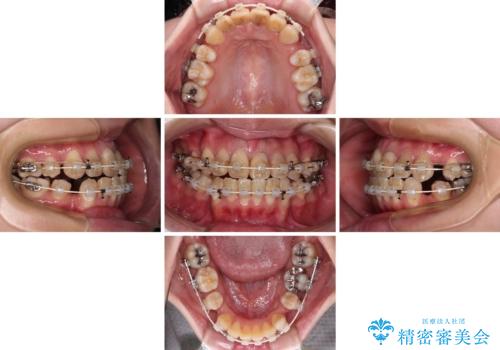

- 前歯の八重歯やデコボコを気にして来院された患者様です。

口元の突出感はありませんが、前歯の重なりが著しいため、目立ちにくい表側のワイヤー装置にて、上下左右の第一小臼歯4本を抜歯して矯正治療を行うこととしました。

上顎前歯4本は、以前むし歯により神経をすべて取り除かれており、その影響で既に変色を起こしている状態でした。

4本とも歯根部先端の骨が炎症により吸収していることがレントゲン写真から示唆されたため、矯正治療後に4本を再根管治療し、その後上顎6歯をオールセラミッククラウンにて補綴治療することとしました。

歯並びだけでなく、歯の色も明るくなり、すっきりとした口元の印象となりました。